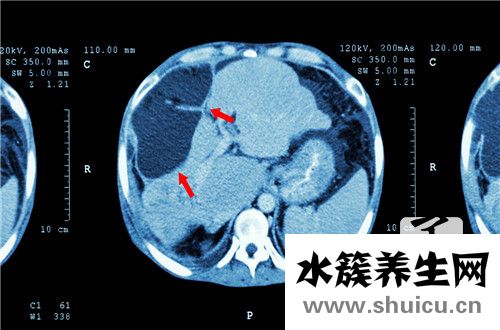

早期肝癌可沒有癥狀的臨床癥狀,一旦出現典型性的臨床癥狀時,已歸屬于中后期肝癌。肝癌的常見癥狀有:肝區隱痛、納呆、削瘦、困乏及其模糊不清原因的發熱、腹脹、腹瀉、黃疸等。

1 .肝區隱痛常由腫瘤生長發育快速使肝外膜支撐力擴大,或腫瘤侵及肝外膜引發。常以中后期肝癌的先發病癥。疼痛多坐落于右脅脅部或劍突下,初起多呈間斷性或持續性隱疼或刺疼。疼痛可時輕時重或一段時間內自主減輕,甚或消退。疼痛多以晚間顯著,有時候要用鎮痛劑。若腫瘤坐落于肝右葉膈頂端則疼痛??煞派湫灾磷蟾觳不蛴冶巢浚蝗裟[瘤坐落于肝左葉則較早出現中上腹脹痛;當腫瘤坐落于肝右葉本質淺層時,一般非常少出現疼痛。肝區隱痛忽然加重,伴觸疼或肌衛征陽性者,應想起是肝破裂或腫瘤流血至肝外膜下。